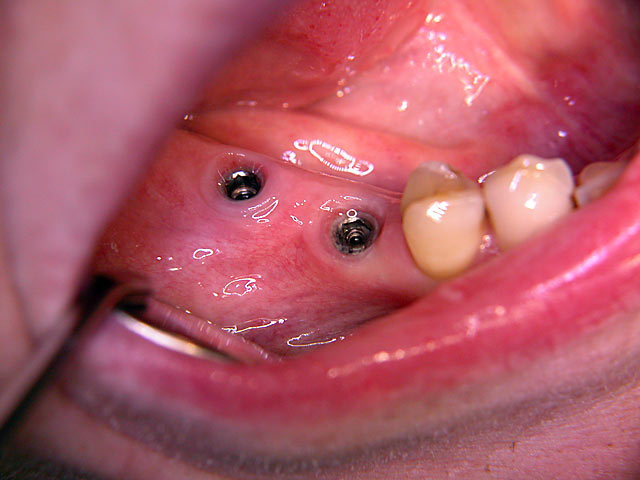

Kurzimplantate und Sofort – Implantate: